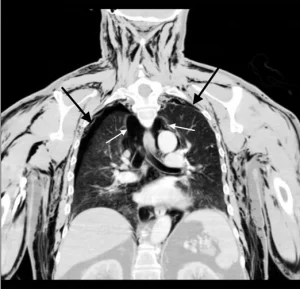

Një ekzaminim zbuloi se të moshuarit i ishin ‘shembur’ të dy mushkëritë dhe ai kishte shumë ajër që qarkullonte brenda gjoksit, gjë që ka të ngjarë të ketë qenë shkaku i ankesës së tij.

Punimi përfundoi: ‘Rasti ynë i pneumoscrotum [ fishkëllimë skotale] nga pneumotoracat dypalëshe spontane të dyshuara [mushkëritë e rrëzuara] ishte i pazakontë. Pacienti ynë kishte një plagë të hapur të skrotalit nga një procedurë e fundit e skrotalit, e cila lejoi që ajri të dilte nga pjesa e tij e barkut dhe rezultoi në shqetësimin e tij’.